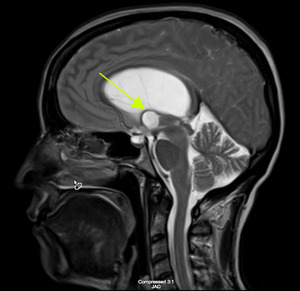

Considerations were given to possible adverse drug reaction to Promethazine, other toxic or infectious etiologies, or structural lesions. Laboratory studies were within normal limits. While waiting to receive a CT scan of her brain, a bedside ocular ultrasound was performed which demonstrated an optic nerve sheath diameter less than 5 mm. without evidence of papilledema. Her CT brain without IV contrast demonstrated dilated lateral ventricles with associated transependymal edema. (Figure 1) An emergent MRI of the brain without contrast was completed to identify a colloid cyst at the level of the Foramen of Monro measuring 1.3 x 1.3 cm. (Figure 2) There was marked obstructive hydrocephalus and cerebral sulcal effacement seen in the image consistent with cerebral edema. The patient was admitted to our hospital for evaluation by the Neurology and Neurosurgery teams.